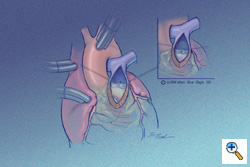

Ventriculotomy

The ventriculotomy is carried onto the RV only as far as necessary to alleviate the infundibular narrowing. This incision in general is 1-2 cm in length, but may be longer in patients with a long, narrowed infundibular septum. The ventriculotomy is also longer if transventricular rather than transatrial VSD closure is to be performed. At the mid-point of the incision, usually the site of the pulmonary valve annulus, the edges of the ventriculotomy are retracted with stay sutures. The functional remnant of pulmonary valve leaflets posteriorly are left intact.

The ventriculotomy is carried onto the RV only as far as necessary to alleviate the infundibular narrowing. This incision in general is 1-2 cm in length, but may be longer in patients with a long, narrowed infundibular septum. The ventriculotomy is also longer if transventricular rather than transatrial VSD closure is to be performed. At the mid-point of the incision, usually the site of the pulmonary valve annulus, the edges of the ventriculotomy are retracted with stay sutures. The functional remnant of pulmonary valve leaflets posteriorly are left intact.